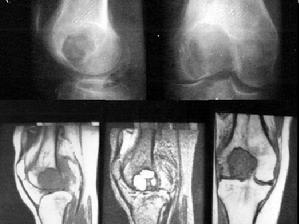

组织细胞纤维瘤是由组织纤维母细胞组成的干骺端错构瘤,目前把病灶小、无临床症状、病变局限于骨膜下或皮质内的称之为干骺端纤维性缺损,而把病灶较大,病变可扩展侵入髓腔而且常合并病理性骨折的称之为非骨化性纤维瘤。